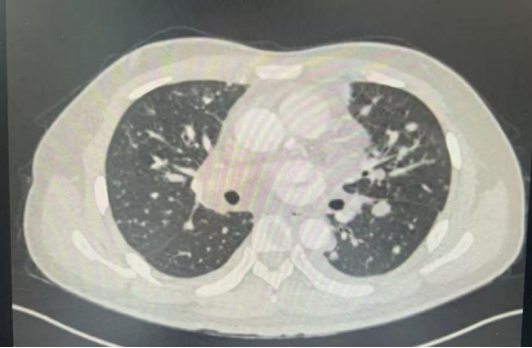

其实,肺结节并不是疾病名称,而是一个影像学术语。肺结节是指影像学表现为最大径≤3 cm的局灶性、类圆形、较肺实质密度增高的实性或亚实性阴影,其可为孤立性或多发性,不伴肺不张、肺门淋巴结肿大及胸腔积液。

图2 版权图片 不授权转载